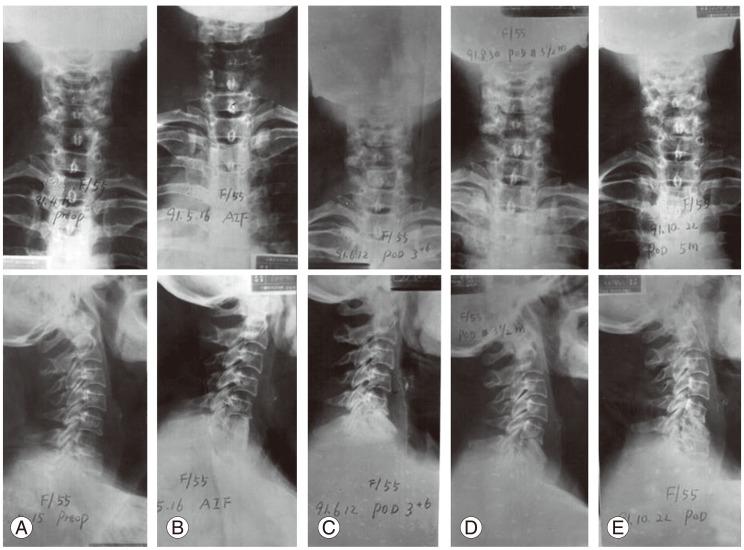

There were intra- and postoperative complications: direct large vessel and neurological injuries (cord, roots, nerves), late thrombophlebitis, various thoracic cavity problems, esophagus and ureter injuries, peritoneum perforation, ileus, wound infections, stabilization failure, increase of deformity and late adjacent joint and bone problems. Thrombophlebitis and sympatheticolysis symptoms and signs in the lower limbs were the most common complications related with anterior lumbar and lumbosacral surgeries. Kyphosis increased in 31.5% of the non-instrumented anterior surgery cases (42% in children and 21% in adults).

术中和术后出现了多种并发症:直接的大血管和神经损伤(脊髓、神经根、神经)、晚期血栓性静脉炎、各种胸腔问题、食管和输尿管损伤、腹膜穿孔、肠梗阻、伤口感染、内固定失败、畸形加重以及晚期相邻关节和骨骼问题。下肢血栓性静脉炎和交感神经松解症状及体征是与前路腰椎及腰骶部手术相关的最常见并发症。在未行内固定的前路手术病例中,31.5%出现驼背加重(儿童为42%,成人为21%)。